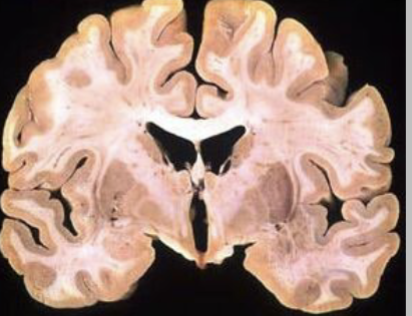

Ventricles

(Spaces between brain)

Cavities filled with cerebrospinal fluid (CSF)

Sewerage system of CNS

Blockages causes hydrocephalus (inflates ventricles, squashing brain)